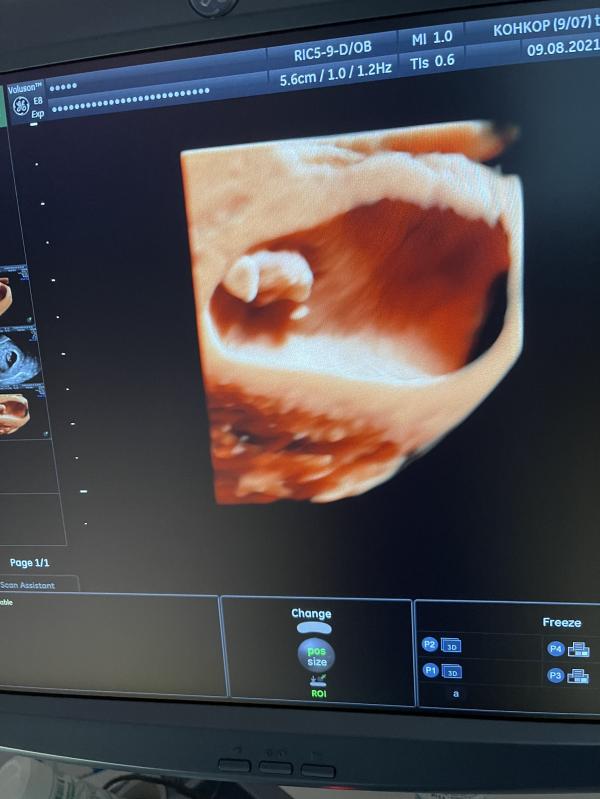

7 неделек ровно , по узи 7.4 ктр 13 , господи как я счастлива 🙏🏻🙏🏻😍

09.08.2021